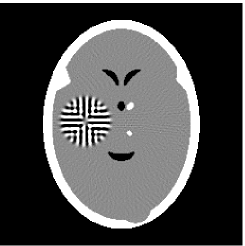

3.2 Ghost phantom

Noiseless projection data: Since the ghost in this phantom is invisible at 22 directions [10, 11], the reconstruction images usually suffer from artifacts. in our simulations, the projection data were collected in 112 and 82 directions: 90 and 60 with equal angle increments from to and 22 specified views in which the ghost is invisible [10]. Iteration procedures were terminated when for the noiseless projections.

The reconstruction images from the noiseless projection data were shown in the Fig. 6. For comparison, Table 3 present the iterations, MSE, Res and running time(RT) of different reconstruction results.

![]() |

| TV-S | TV-S |

| TV-PPS | TV-PPS |

| Algorithm | TV-S | TV-PPS | TV-S | TV-PPS |

|---|---|---|---|---|

| projections | 112 | 112 | 82 | 82 |

| iterations | 24 | 19 | 33 | 32 |

| MSEs | 0.0056 | 0.0026 | 0.0108 | 0.0083 |

| RT(min) | 16.82 | 13.89 | 10.83 | 10.87 |